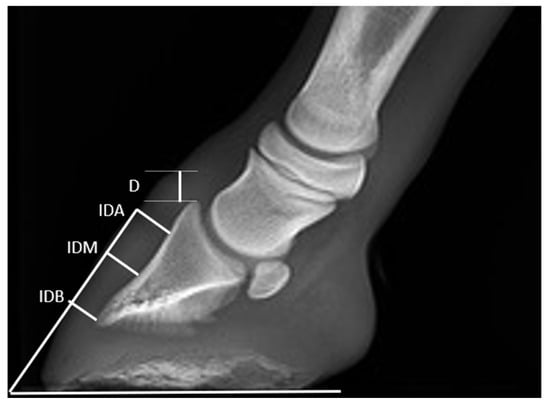

| D | IDA | IDM | IDB | |

|---|---|---|---|---|

| T0 | 8.8 ± 1.7 | 9.8 ± 1.1 | 10.0 ± 1.2 | 6.6 ± 0.5 |

| p-value | 0.95 | 0.86 | 0.17 | 0.47 |

| T1 | 7.4 ± 1.4 | 10.5 (10–11) | 10.6 ± 1.1 | 6.9 ± 0.8 |

| p-value | 0.83 | 0.02 | 0.60 | 0.57 |

| T2 | 7.2 ± 1.6 | 11 (10.1–11) | 10.5 ± 1.2 | 7 (7–7.2) |

| p-value | 0.54 | 0.001 | 0.55 | 0.001 |

| T3 | 6.6 (6.2–7) | 11.0 ± 1.4 | 10.8 ± 1.1 | 7.5 ± 0.5 |

| p-value | 0.02 | 0.16 | 0.50 | 0.12 |

| T4 | 6.7 ± 1.1 | 11.5 ± 1.3 | 10.7 ± 1.9 | 8.8 ± 1.7 |

| p-value | 0.72 | 0.97 | 0.08 | 0.85 |

| T5 | 7.8 ± 0.9 | 12.0 ± 1.4 | 11.8 ± 1.5 | 9.5 (9–10) |

| p-value | 0.27 | 0.16 | 0.22 | 0.02 |

| T6 | 9.0 ± 0.8 | 12.5 ± 1.7 | 13.0 ± 0.8 | 11.3 ± 1.5 |

| p-value | 0.68 | 0.19 | 0.68 | 0.22 |